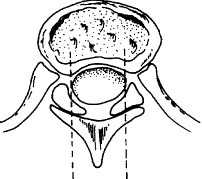

3.CT和CTM檢查 可充分反映脊髓的形態變化並能顯示骨化灶與脊髓等結構間的關係兩側椎板前方的骨化塊可突入椎管通常骨化在椎間孔椎間盤或小關節平面處較為顯著。按骨化位置及形態可分為瀰漫型(最多見)側方型(次多見)和結節型。